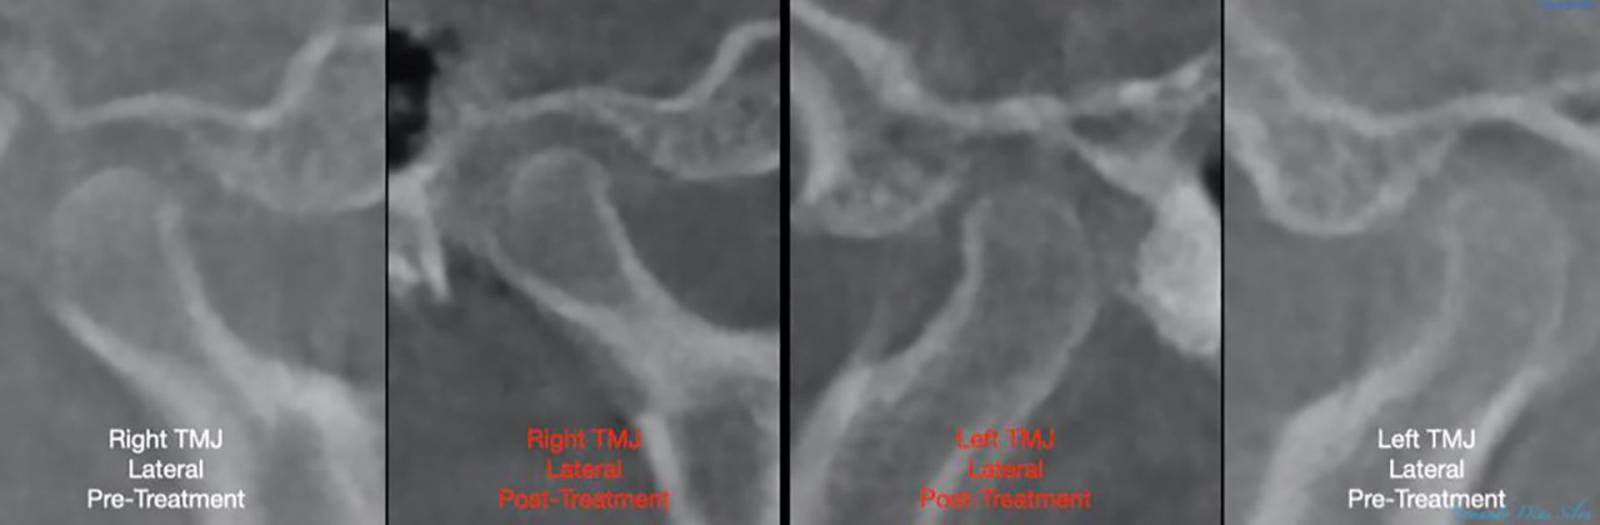

- No changes in condyle position

No changes in condyle position

No changes in condyle position